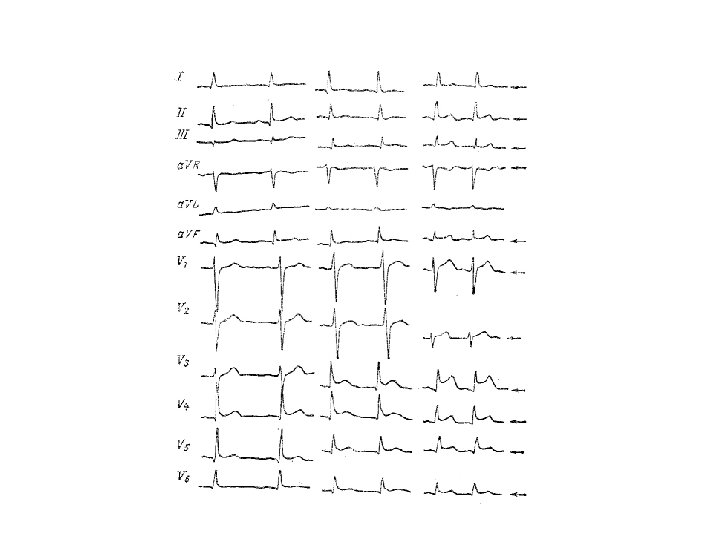

Изменения ЭКГ при онкологических поражениях сердца и перикарда